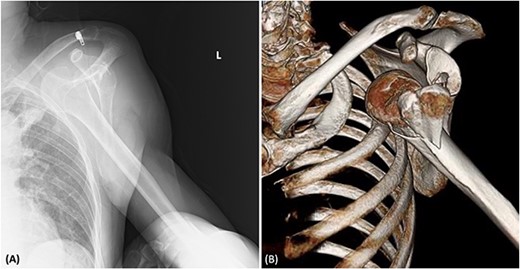

A 58-year-old man, a smoker with a history of lobectomy for lung cancer, presented to our emergency centre with complaints of left shoulder pain after striking his left shoulder in a fall after alcohol consumption. On arrival at the hospital, his blood pressure was 107/69 mmHg and his pulse rate was 78 beats/min. There was no cyanosis in his extremities. The radial artery pulse was not checked during the initial examination. Blood test results revealed a haemoglobin level of 13.2 g/dL. Radiography and computed tomography (CT) showed an anterior dislocation of the left shoulder joint with a humerus fracture (Fig. 1). The orthopaedic team did not suspect vascular injury based on physical examination and blood test, and did not perform a contrast enhanced CT. Their attempts to perform closed reduction for the shoulder dislocation were unsuccessful. Therefore, open reduction was performed under general anaesthesia.

(A) Radiography showing the dislocation of the left shoulder joint. (B) 3D-CT showing a humeral fracture.